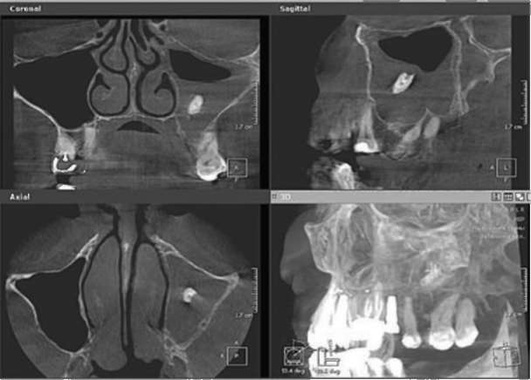

Хроническое воспаление верхнечелюстной пазухи, как правило, развивается при переходе острого воспаления в хроническое, но возможно и без предшествующей ярко выраженной острой стадии заболевания. Пациенты жалуются на боли и чувство тяжести в затылочной области, однако у многих пациентов заболевание протекает, в принципе, бессимптомно, за исключением периодических эпизодов нарушения носового дыхания (рис. 5.86, 5.87).

image

Рис. 5.86. .Хронический одонтогенный верхнечелюстной синусит слева

Рис. 5.87. Хронический одонтогенный верхнечелюстной синусит слева. Инородное тело верхнечелюстной пазухи (корень зуба).

Наибольшую информацию для постановки диагноза дает радиологическое исследование. Вместе с тем нередко традиционные (двухмерные) радиологические исследования не обнаруживают четких изменений. Если хроническое течение одонтогенного синусита связано с наличием инородных тел (корней зубов, пломбировочного материала, фрагментов эндодонтического инструмента), их обнаруживают на КЛКТ. Среди всех форм ВС именно при перфоративной форме синусита преобладают первично-хронические формы. Перфоративные синуситы, связанные с удалением зуба, нередко травматичным, оставляют после вмешательства дефект альвеолярного отростка.